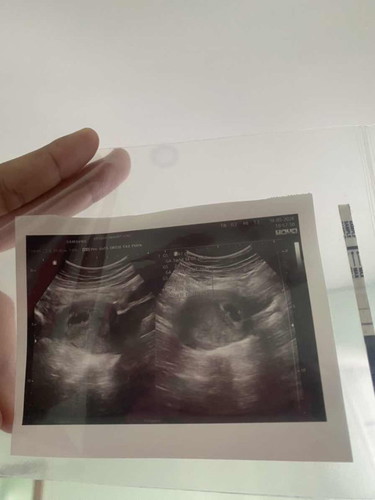

ของหนูมาล่าสุด 18 มีนา ซาวน์ 26 เมษา เจอแต่ถุงตั้งครรภ์กับถุงไข่แดงคะ วันนี้ซาวน์ วันที่ 24 พฤษภาคม เพิ่งมาเจอคะ อายุครรภ์ 9 สัปดาห์ 4 วันคะ

ตัวเองพึ่งไปวันนี้หรอคะ แข็งแรงทั้งคู่น้าา 🤍

อายุครรภ์เท่ากันเลยค่ะแต่เราซาวเห็นน้องเป็นตัวเเล้วนะค่ะแม่